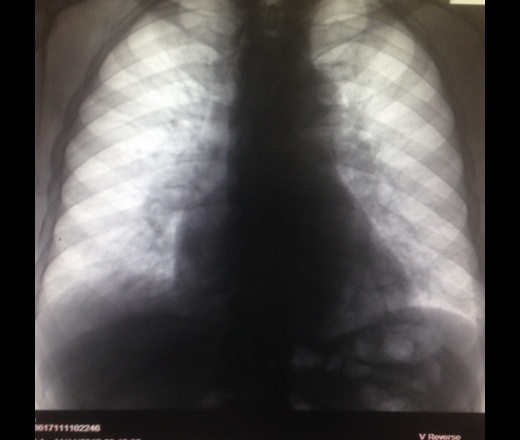

Гидроторакс: Аускультация и диагностика